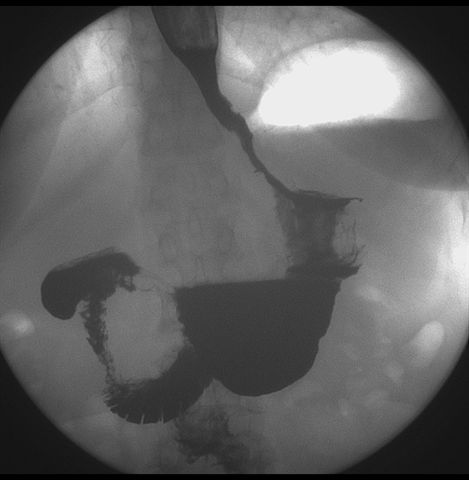

标题: X6872:F,69y,胃部不适。

胃窦至幽门段胃壁僵硬,扩张受限,局部纠集粘破坏,呈杵状。提示溃疡癌变可能性大。

胃窦癌可能性大,建议胃镜活检。钡剂太稀,吃的有点多。

支持考虑胃窦癌可能,胃内滞留液太多,胃窦部僵硬。

瀑布型胃,胃粘膜那是一个乱,窦部充盈不好,第16幅窦部粘膜反倒又很顺,先定个胃炎胃窦炎胃窦癌待排之类,建议进一步作胃镜检查。

胃窦部见钡池影,局部粘膜紊乱,纠集呈杵状改变,胃壁扩张受限,胃窦癌可能性大,建议胃镜检查.

胃窦部管腔扩张度较差,形态略有改变,胃窦粘膜显示欠佳,胃窦部占位可能性大,结合胃镜活检。

胃窦部狭窄、稍僵硬,考虑胃窦癌?建议胃镜检查。

北京肿瘤医院胃镜诊断皮革胃。